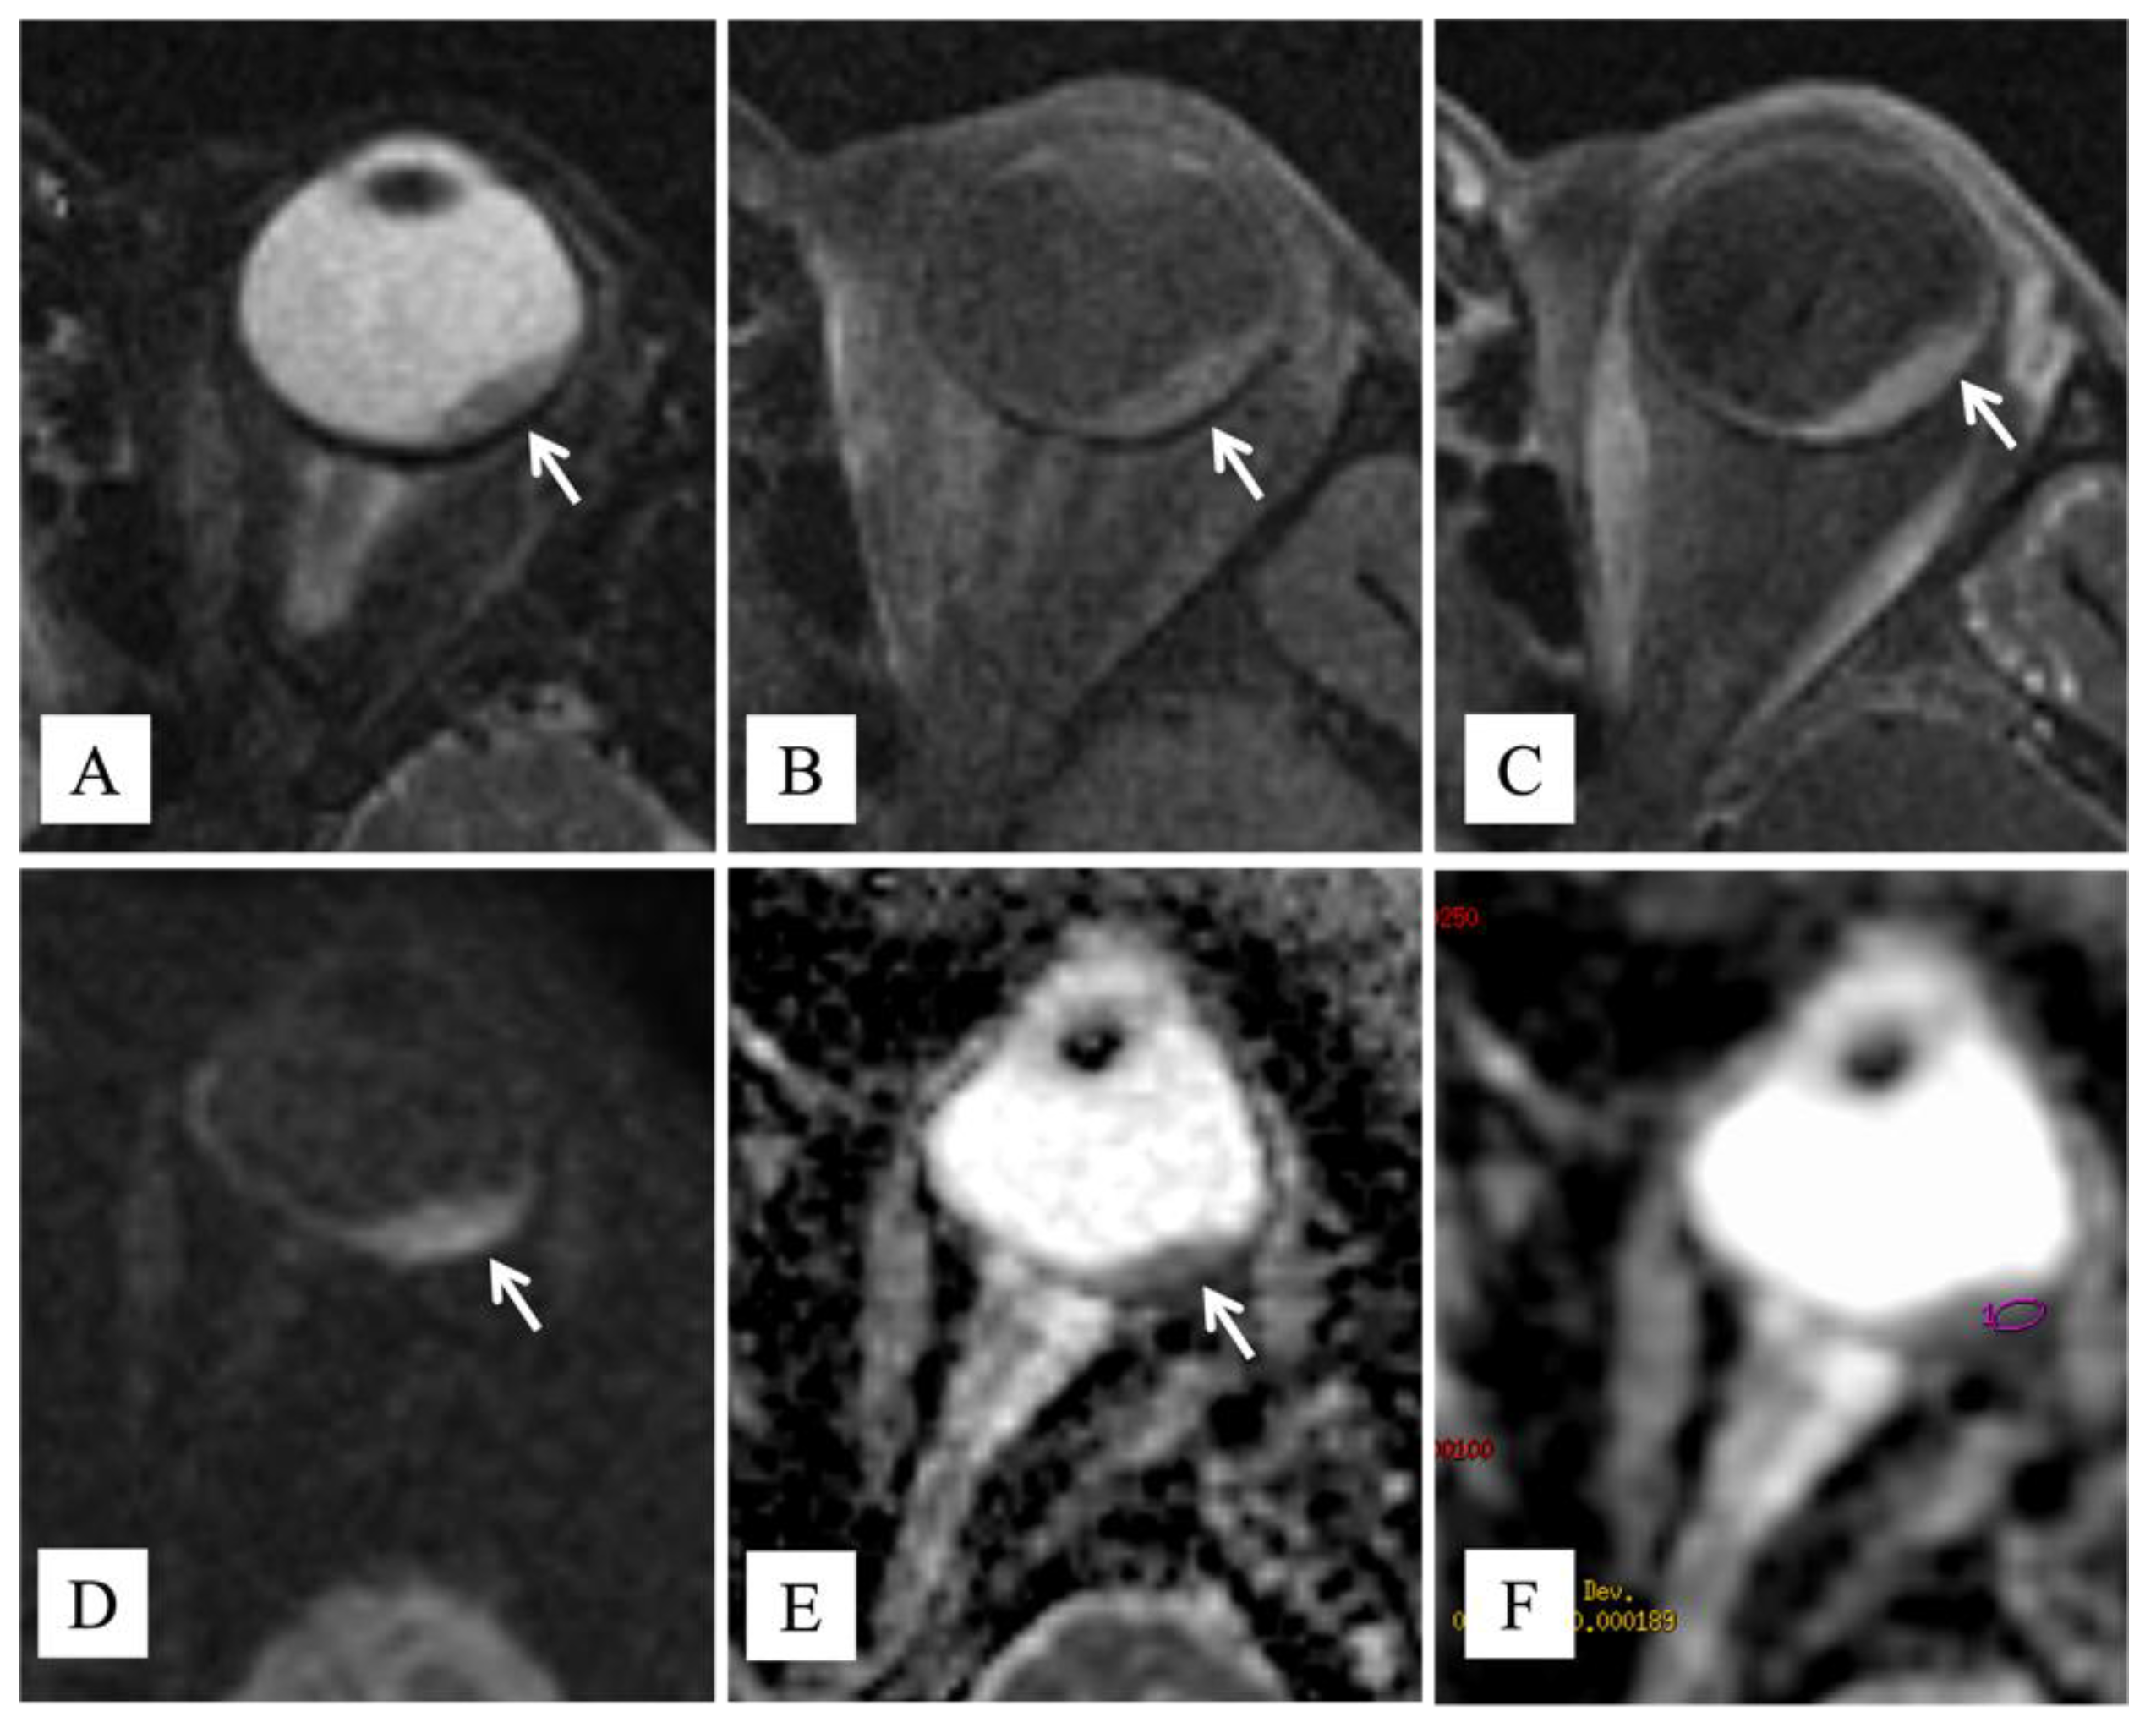

- Foti, P.V.; Travali, M.; Farina, R.; Palmucci, S.; Spatola, C.; Raffaele, L.; Salamone, V.; Caltabiano, R.; Broggi, G.; Puzzo, L.; et al. Diagnostic methods and therapeutic options of uveal melanoma with emphasis on MR imaging-Part I: MR imaging with pathologic correlation and technical considerations. Insights Imaging 2021, 12, 66. [Google Scholar] [CrossRef] [PubMed]

- Sepahdari, A.R.; Kapur, R.; Aakalu, V.K.; Villablanca, J.P.; Mafee, M.F. Diffusion-weighted imaging of malignant ocular masses: Initial results and directions for further study. AJNR Am. J. Neuroradiol. 2012, 33, 314–319. [Google Scholar] [CrossRef] [Green Version]

- Erb-Eigner, K.; Willerding, G.; Taupitz, M.; Hamm, B.; Asbach, P. Diffusion-weighted imaging of ocular melanoma. Investig. Radiol. 2013, 48, 702–707. [Google Scholar] [CrossRef]

- Foti, P.V.; Farina, R.; Coronella, M.; Palmucci, S.; Montana, A.; Sigona, A.; Reibaldi, M.; Longo, A.; Russo, A.; Avitabile, T.; et al. Diffusion-weighted magnetic resonance imaging for predicting and detecting the response of ocular melanoma to proton beam therapy: Initial results. Radiol. Med. 2015, 120, 526–535. [Google Scholar] [CrossRef]

- Foti, P.V.; Longo, A.; Reibaldi, M.; Russo, A.; Privitera, G.; Spatola, C.; Raffaele, L.; Salamone, V.; Farina, R.; Palmucci, S.; et al. Uveal melanoma: Quantitative evaluation of diffusion-weighted MR imaging in the response assessment after proton-beam therapy, long-term follow-up. Radiol. Med. 2017, 122, 131–139. [Google Scholar] [CrossRef] [PubMed]